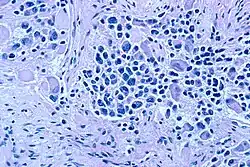

Neuroblastoma należy do tzw. guzów drobnookrągłoniebieskokomórkowych: charakterystyczne dla obrazu histologicznego są skupiska małych (nieco większych od limfocytów) prymitywnych komórek z okrągłymi lub owalnymi hiperchromatycznymi jądrami i małą ilością cytoplazmy. Ziarnista chromatyna przyrównywana jest do ziaren soli i pieprzu (ang. salt and pepper chromatin). Widoczne są liczne figury podziałów mitotycznych, komórki apoptotyczne i tak zwane rozetki Homera Wrighta, złożone z komórek nowotworowych wianuszkowato otaczających bladoróżowy fibrylarny materiał utworzony z ich cienkich wypustek cytoplazmatycznych.

W badaniu immunohistochemicznym stwierdza się dodatnią reakcję komórek nowotworu na obecność synaptofizyny, chromograniny, neurofilamentów i neuronospecyficznej enolazy (NSE); ujemna jest reakcja na wimentynę, desminę i keratynę.